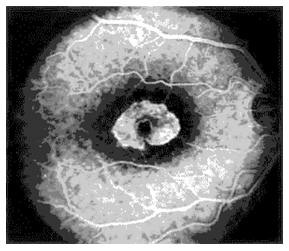

Recirculation phase & late phase: (Figure 11) Recirculation phase: Begins about 30 seconds after the dye injection, fluorescence within the vessels reduces as lower concentration of fluorescein recirculates Late phase: Retinal vessels are empty of the fluorescein dye by 10 minutes after injection, disc remains hyper fluorescent in late films due to staining .

Figure 11 Recirculation phase & late phase.